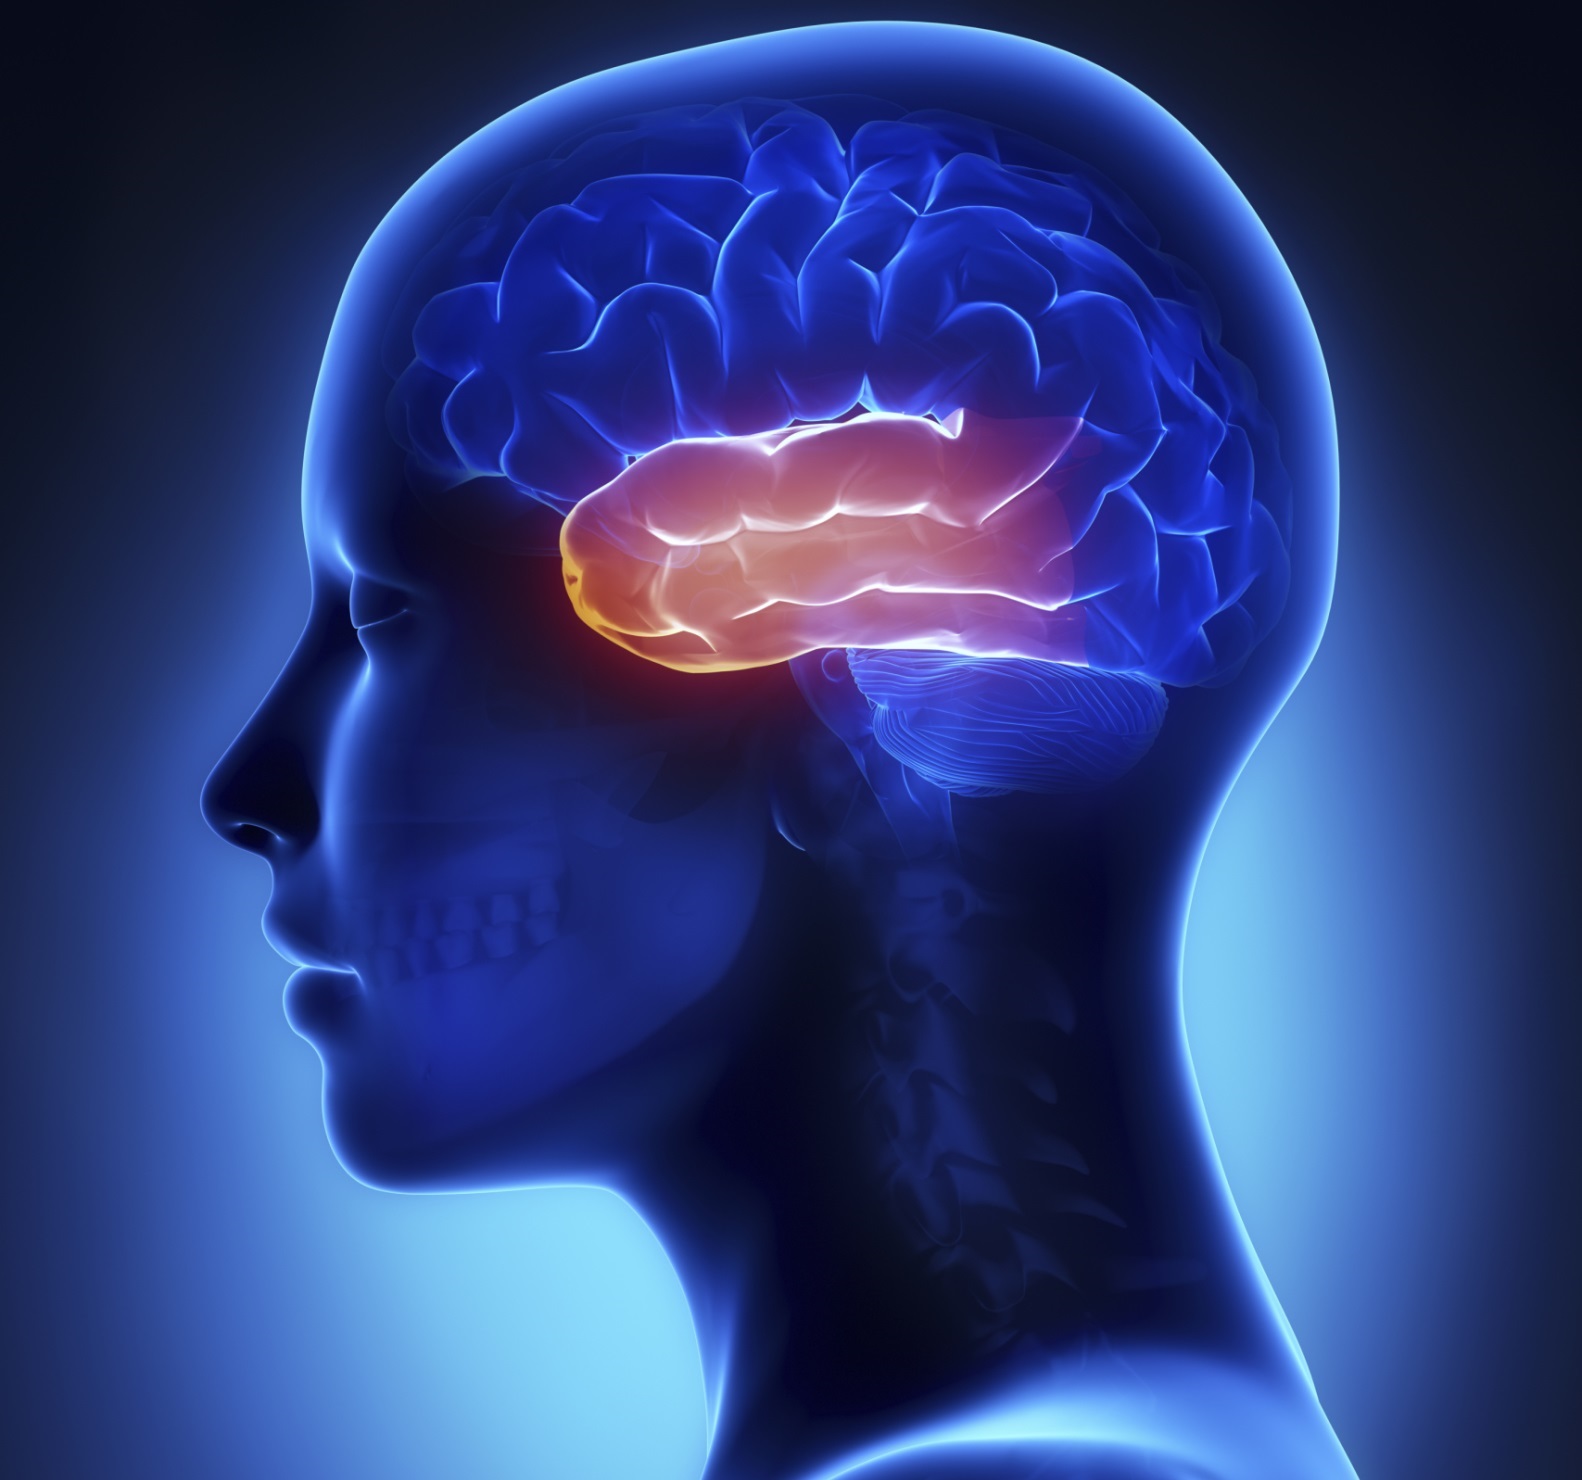

What Is Temporal Lobe

What Is Temporal Lobe

Temporal Lobe Anatomy Location Function Damage Epilepsy

Temporal Lobe SpinalCord

Temporal Lobe SpinalCord

Temporal Lobe The Definitive Guide Biology Dictionary

Temporal Lobe Function Location And Structure

Temporal Lobe

Temporal Lobe What Is It Location Structure Functions Injuries

Temporal Lobe What Is It Location Structure Functions Injuries